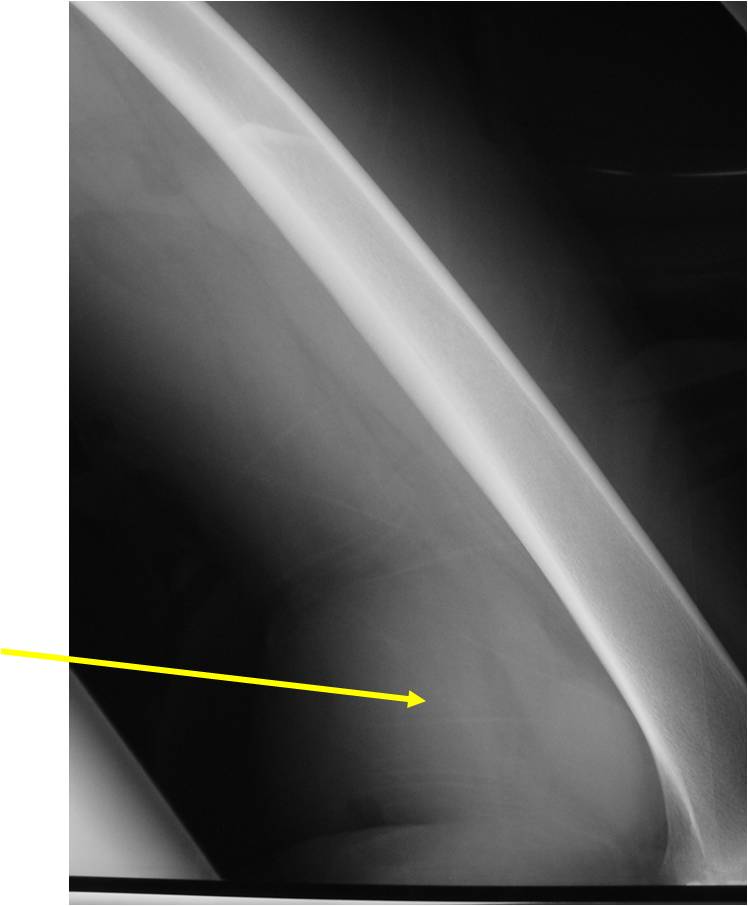

- Aggressive motheaten to permeative lesion

- Indistinct border in most cases

- Osseous destruction with a soft tissue component

- Chondroid matrix calcification may be present (60-70% of cases)

- Soft tissue mass

(Right Arrow) Cartilaginous Component